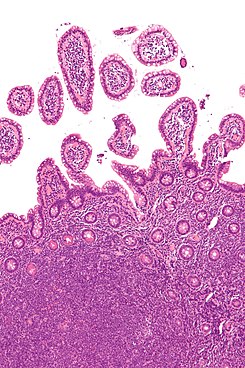

• Linfoma No-Hodgkin: empleo de emisores gamma para su diagnóstico

Ximena Camacho, Agustina Banchero, Eloisa Riva, Paola Audicio, Pablo Cabral

46-57

DOI: https://doi.org/10.35954/SM2015.34.1.7